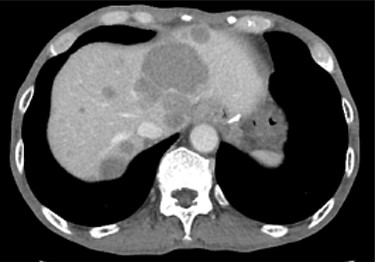

A 74-year-old man presented to the hospital for follow-up esophagogastroduodenoscopy (EGD) after Helicobacter pylori eradication. EGD revealed a large necrotic ulcerated mass at the cardia of the stomach (Fig. 1). Endoscopic biopsy revealed a malignant tumor negative for cytokeratin AE1/AE3, CD45, chromogranin A and synaptophysin on immunohistochemical (IHC) staining, and initial diagnosis was poorly differentiated adenocarcinoma. Physical examination, routine blood investigations and serum tumor marker levels, including carcinoembryonic antigen, CA-125 and CA 19-9, were normal. Abdominal computed tomography (CT) showed thickness of the stomach wall directly below the esophagus (Fig. 2, red arrow). Enlarged lymph nodes and distant metastatic lesions were absent. Radical surgery including total gastrectomy and D2 lymph node dissection was performed. Surgical specimens demonstrated a whitish amelanotic mass with central ulceration, present at EGJ, measuring 38 mm × 30 mm and protruding into the gastric lumen (Fig. 3A). Histological examination revealed polygonal and round neoplastic cells with round nuclei and prominent nucleoli nestled within the esophageal squamous epithelium, thus forming an ‘in situ’ lesion. No melanin deposition was found in the neoplastic cells. Immunohistochemically, neoplastic cells were positive for HMB45 and S-100 (melanoma markers; Fig. 3B–D). The final diagnosis was primary amelanotic malignant melanoma of esophagus, T2, N0 and M0 (UICC [International Union against Cancer] classification system, 7th ed.). Four months after surgery, abdominal CT revealed multiple liver metastases. The patient received seven cycles of nivolumab monotherapy, with two subsequent cycles of nivolumab and ipilimumab. Liver metastases were initially controlled by immunotherapy, but they eventually worsened, as assessed by the Response Evaluation Criteria in Solid Tumors ver. 1.1 (Fig. 4).

Contrast-enhanced CT showing progression of multiple cystic metastases in the liver.